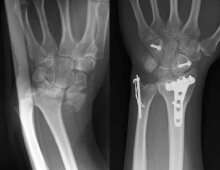

当院では平成22年4月1日から四肢外傷センターを開設いたしました。センターでは骨折をはじめ、皮膚、腱、靱帯、神経損傷などの患者様の治療にあたります。また、偽関節や骨髄炎、変形治癒などの四肢外傷後の合併症に対してもマイクロサージャリーや仮骨延長法などの先進医療を駆使した治療を施行します。手や肘の疾患に関しましては、外傷のみならず一般の疾患(手のしびれや腱鞘炎、指の関節炎、先天異常など)に対しても専門的な治療を行います。

手は人間の第二の脳とも言われるように体の中で最も繊細で複雑な運動器官と感覚器官を合わせ持っています。そのため外傷や疾病により障害された手の機能を回復させる治療には高度な専門知識と技術が必要とされます。センターでは日本手外科学会専門医が手や肘の疾患の治療にあたります。 - マイクロサージャリーとは

肉眼では操作困難な直径0.5~3mm前後の血管や神経などを顕微鏡下に操作し修復する技術を指します。この技術を用いることにより損傷された血管や神経の修復のみならず、切断肢(指)再接着や外傷などで失われた体の部位を再建する組織移植などが可能となっています。センターではマイクロサージャリーを駆使した最先端の治療を行います